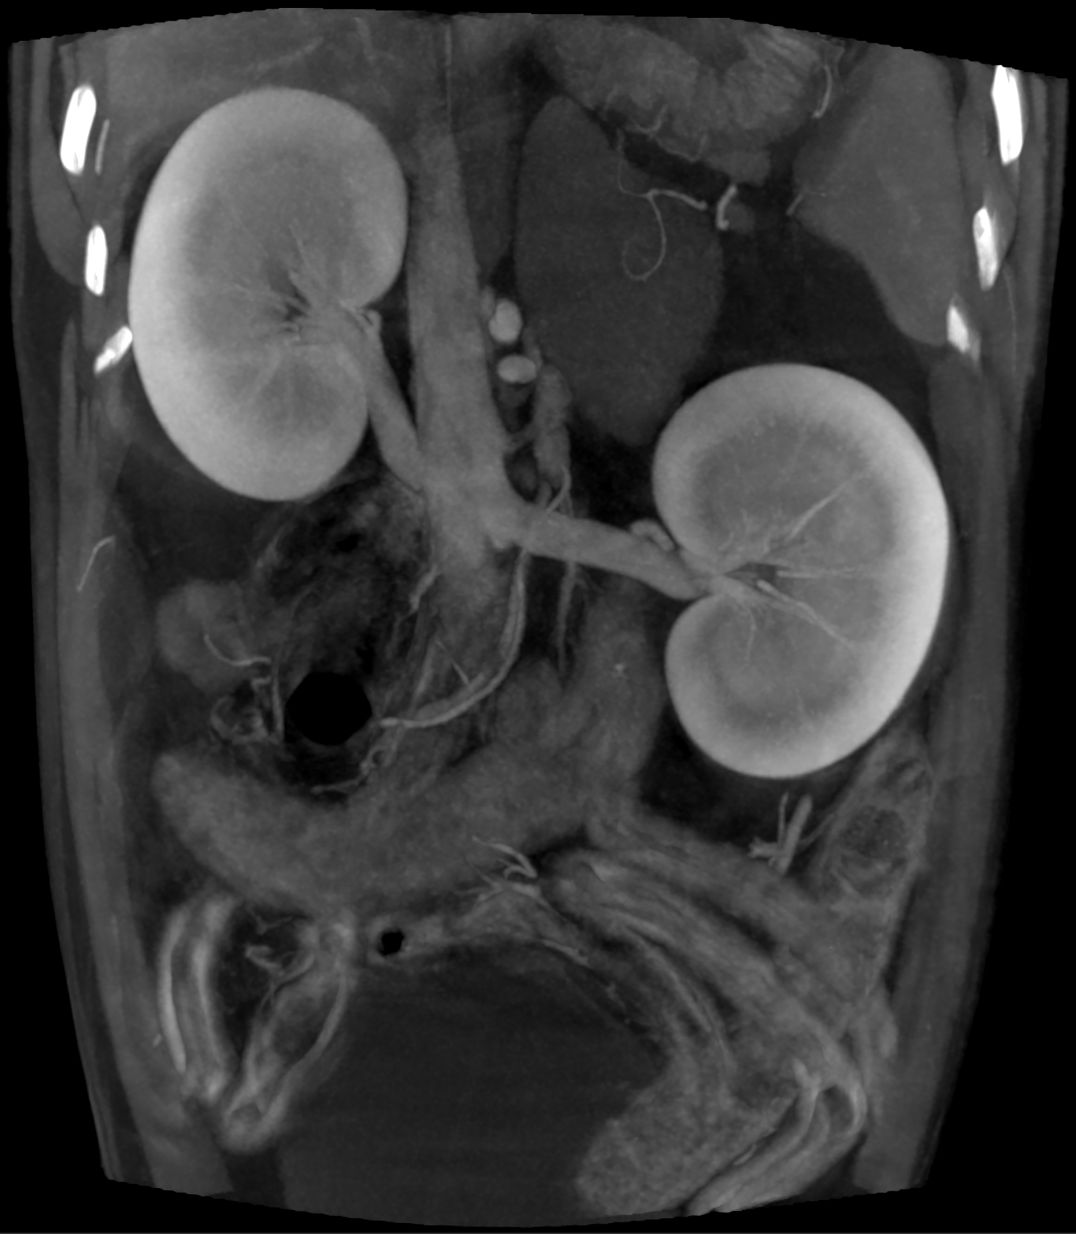

Kidneys

DO NOT ACCEPT less than the BEST

We have the most advanced imaging available, which allows us to see bones, blood vessels, organs and joints with the best resolution and clarity available.  Our scans take less than ONE MINUTE and is the best decision you can make for your pets care.